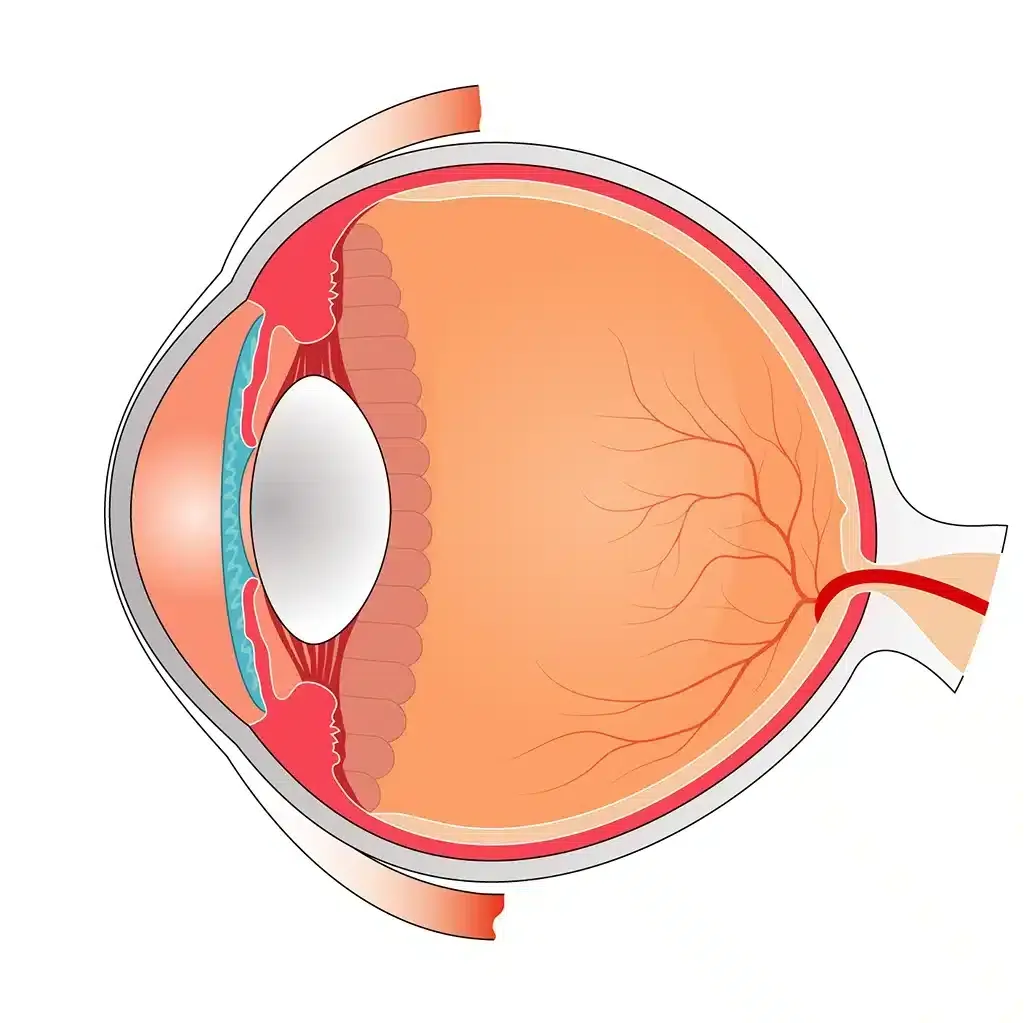

КТ-графики и изображение строения глаза